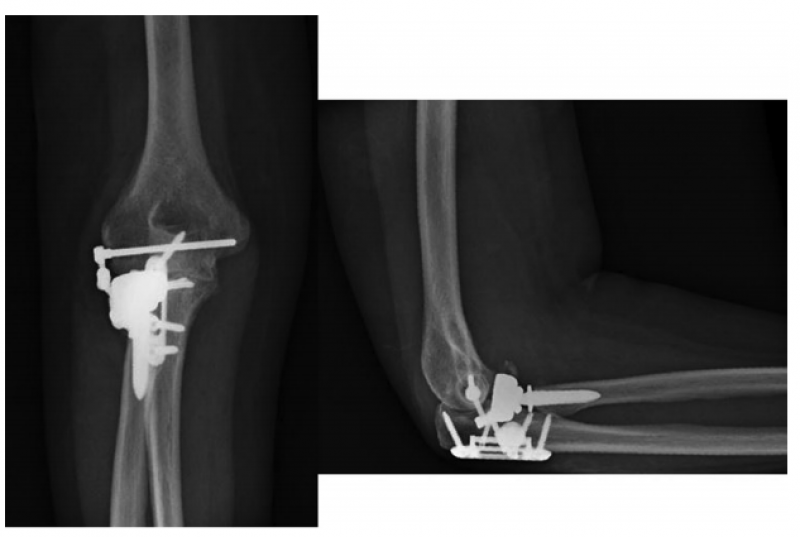

7、Pasternack等提出了一种型的肘关节内固定架,只有10例患者(6例是三联征,2例新鲜肘关节脱位,1例陈旧肘关节脱位,1例外髁骨折),2016年获得FDA批准。平均术后74天后取出。内固定架能够减少外固定架带来的术后并发症,同时能够维持肘关节的稳定性,但由于初始损伤比较重,由于其他各种原因导致的二次手术率仍然较高。

1、肘关节旋转轴三维定位

国内蒋协远教授团队在世界上率先采用三维导航机器人进行肘关节旋转中心定位。TiRobot机器人导航辅助肘关节旋转中心轴定位能够极大地降低主观判断造成的旋转轴偏移,提高轴心定位精准度,减少反复透视验证的过度辐射及反复调整轴心导针的骨质破坏,避免可能的血管、神经损伤,显著减小降低术后肘关节活动阻力,并减少外固定针松动、断裂及外固定架断裂等并发症的发生率,从而整体提高治疗效果。